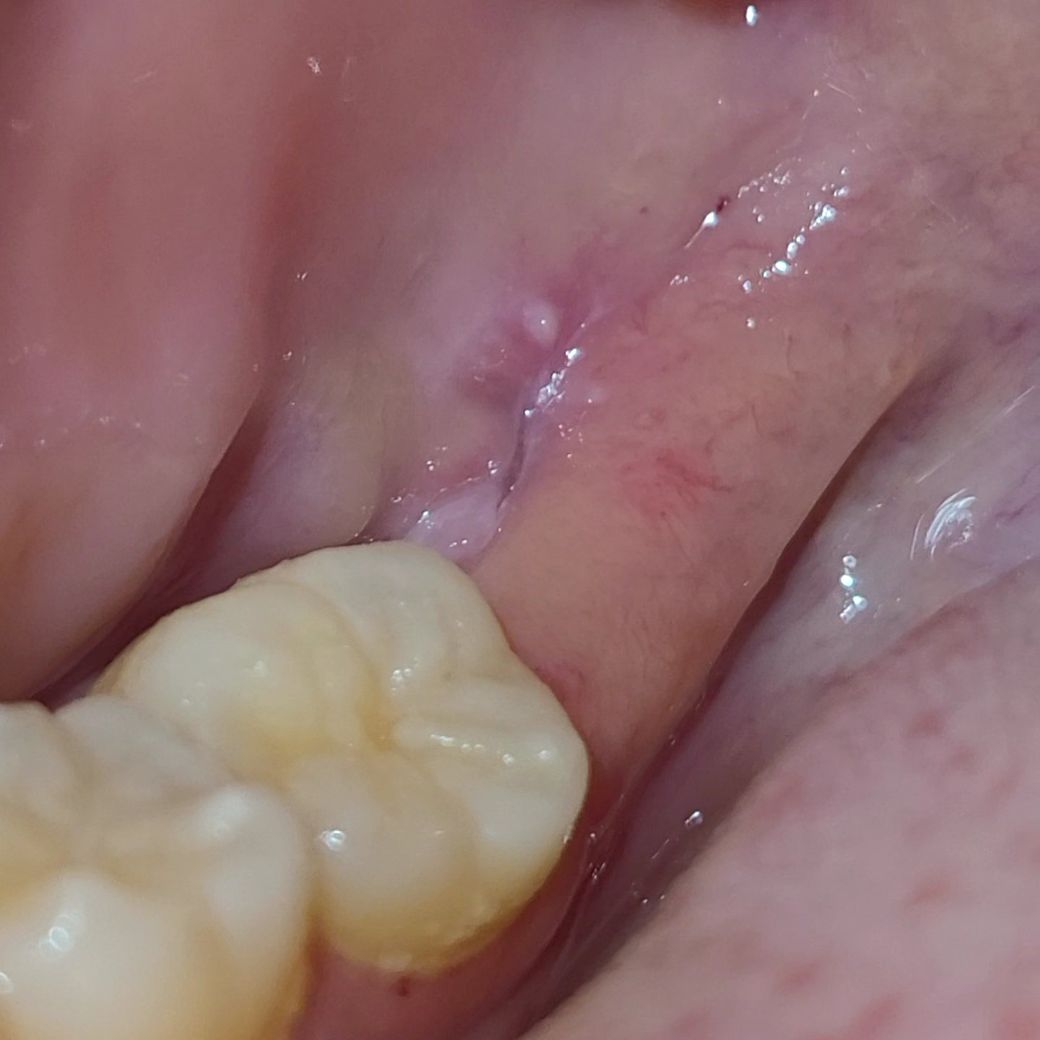

사랑니 발치 후 잇몸에 딱딱한게 보여요

매복 사랑니 발치 후 13일차입니다

통증도 사라지고 붓기와 멍도 잘 회복되었는데

발치한 곳 바로 앞쪽 잇몸에

하얗고 딱딱한게 보이더라구요

첫번째 사진은사랑니 뽑은 자리 주위가 완전히 아물지 않은 것으로 보입니다.

두번째 사진은 사랑니 뽑은 자리에 흔적이 아직 남아 있는 것으로 보입니다.

13일째 약 2주 정도 지났으니 정상적인 치유 과정으로 보입니다.

사랑니 발치하고 나서 잇몸뼈가 약간 튀어나오신것같습니다. 사랑니 발치후 잇몸뼈가 잇몸밖으로 더 자라나는경우가 가끔 발생합니다. 크게 걱정할일은 아니시고, 불편하시면 치과 가셔서 마취후 간단히 제거하시면됩니다.

사진상에서는 구내염으로 보입니다. 증상이 없다면 별다른 문제는 되지 않으며 대체로 수일내에 회복되는편입니다. 그러나 만약 증상이 심해서 불편하거나 2주 이내로 회복이 되지 않는 경우라면 치과에서 검사를 받아보시는게 좋습니다.

구내염같이 보이나, 딱딱한것이 확실하다면 구내염은 아닙니다.

그렇다면 안에 잇몸뼈가 노출된 것이거나, 치아뿌리가 남은것일 수 있습니다.

하지만 위치상으로 치아뿌리일것같진 않고, 딱딱한것이 확실하다면 잇몸뼈일 가능성이 가장 높습니다.

잇몸뼈의 돌출로 보입니다.

잇몸쪽으로 뼈조각이 돌출된것일 수도 있고 치아 파편인것을 수도 있습니다.